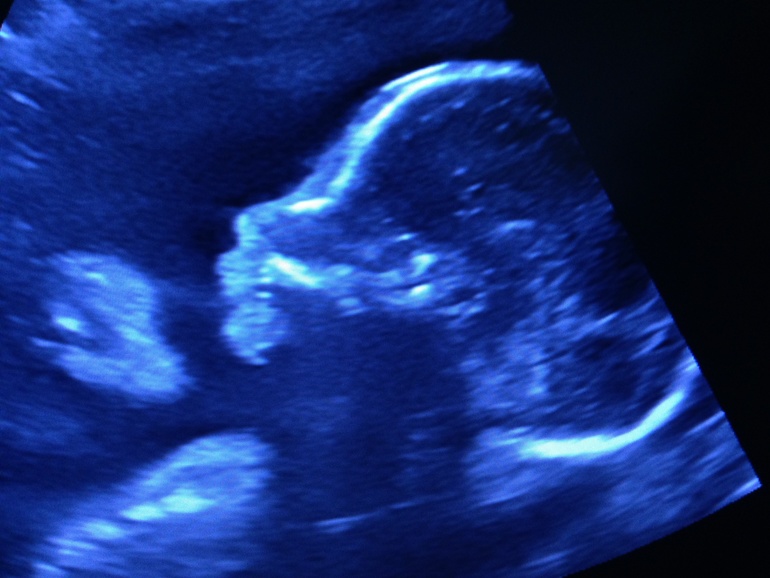

Наша крошка) я с узи без фото не ухожу))